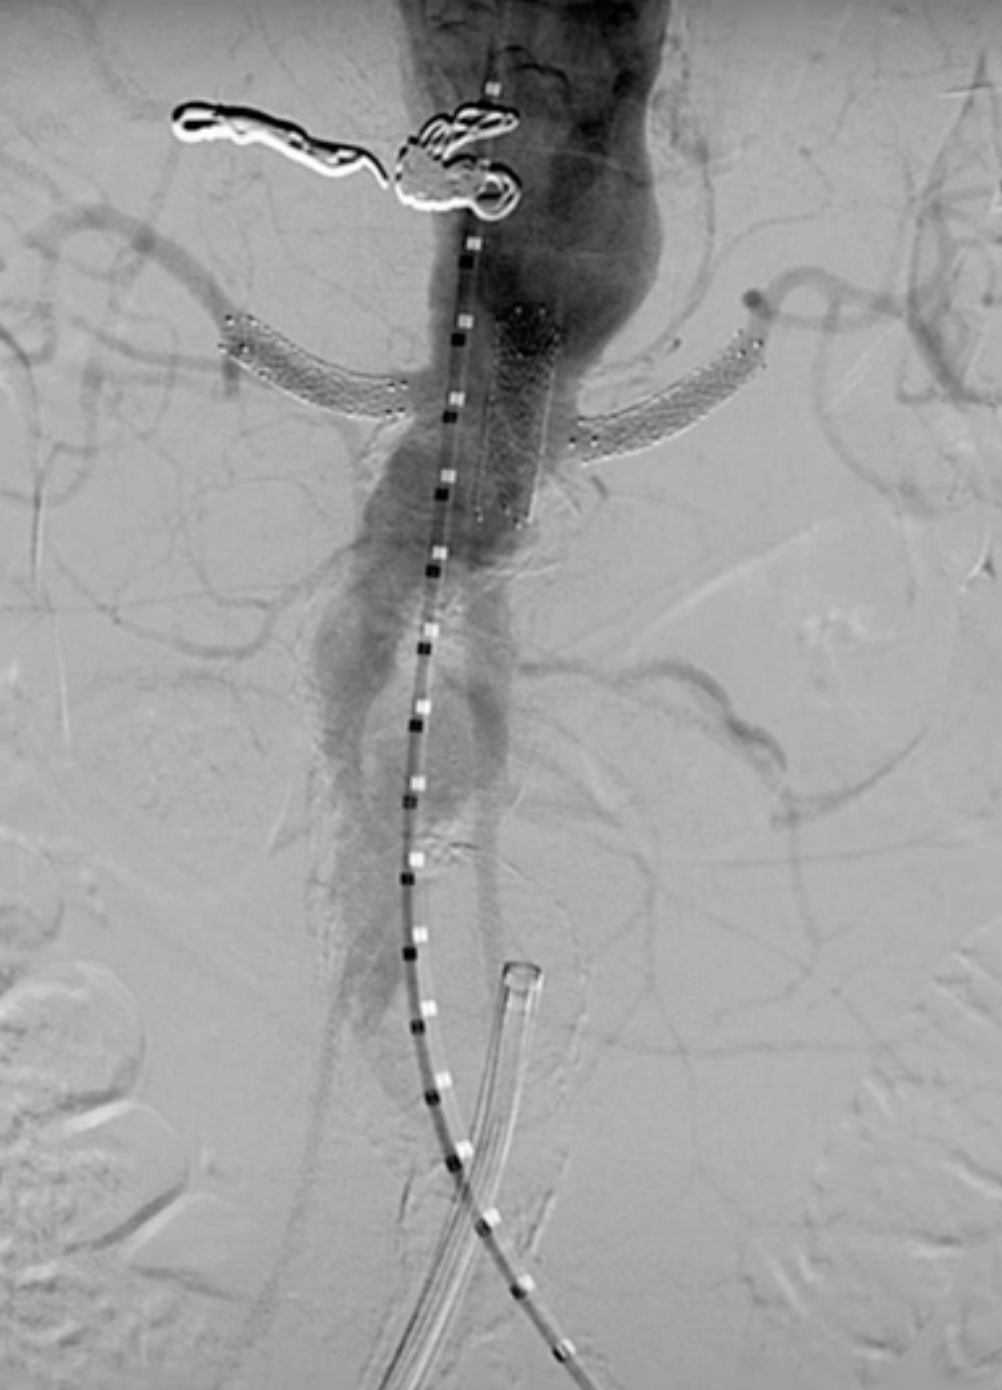

术前造影

使用12Fr DrySeal Flex亲水涂层导引鞘和7F可调弯鞘配合导丝超选入内脏动脉。

在左肾动脉预植入Visi pro裸支架。

对其他目标内脏血管重复上述操作,在较弯曲的血管中选择较短的支架更为方便。在肠系膜上动脉进行必要的侧位造影。